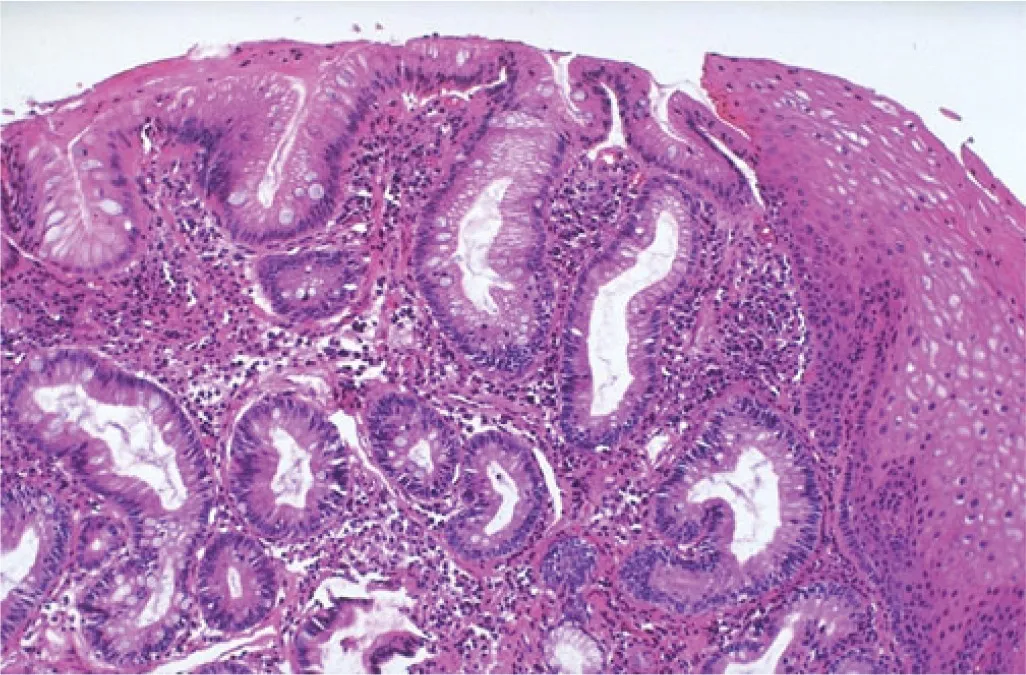

Fluorescent In-Situ Hybridization (FISH) is performed on samples of Barrett’s epithelium of the esophagus, determining the risk of developing dysplasia and malignancy in patients with known Barrett’s Esophagus.

This Assay is tested using cytology brushings from known Barrett’s esophagus (BE) patients and/or suspected BE nodules to help determine the risk of developing dysplasia and adenocarcinoma. Cytology specimens collected via endoscopic brushing result in more comprehensive and wide area tissue sampling than biopsies alone. FISH testing is performed on the cytology sample as an adjunct to the four quadrant biopsies. Studies have shown progression to High-Grade Dysplasia & Esophageal Adenocarcinoma in spite of no dysplasia being seen on traditional biopsies within 33 months of significant genetic abnormalities and if polysomy is seen on the FISH testing. Barrett’s FISH uses probes that help identify genes, including MYC, p16, HER2, and ZNF217.